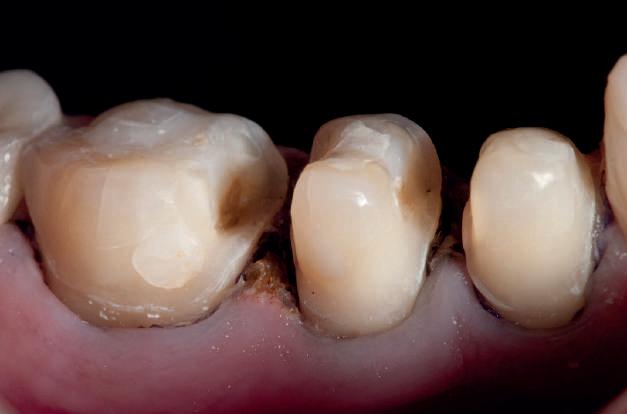

HYBRID COMBINATION RESTAURATIONS

Vonlay-uri: o alternativă conservatoare estetică la coroanele cu acoperire totală